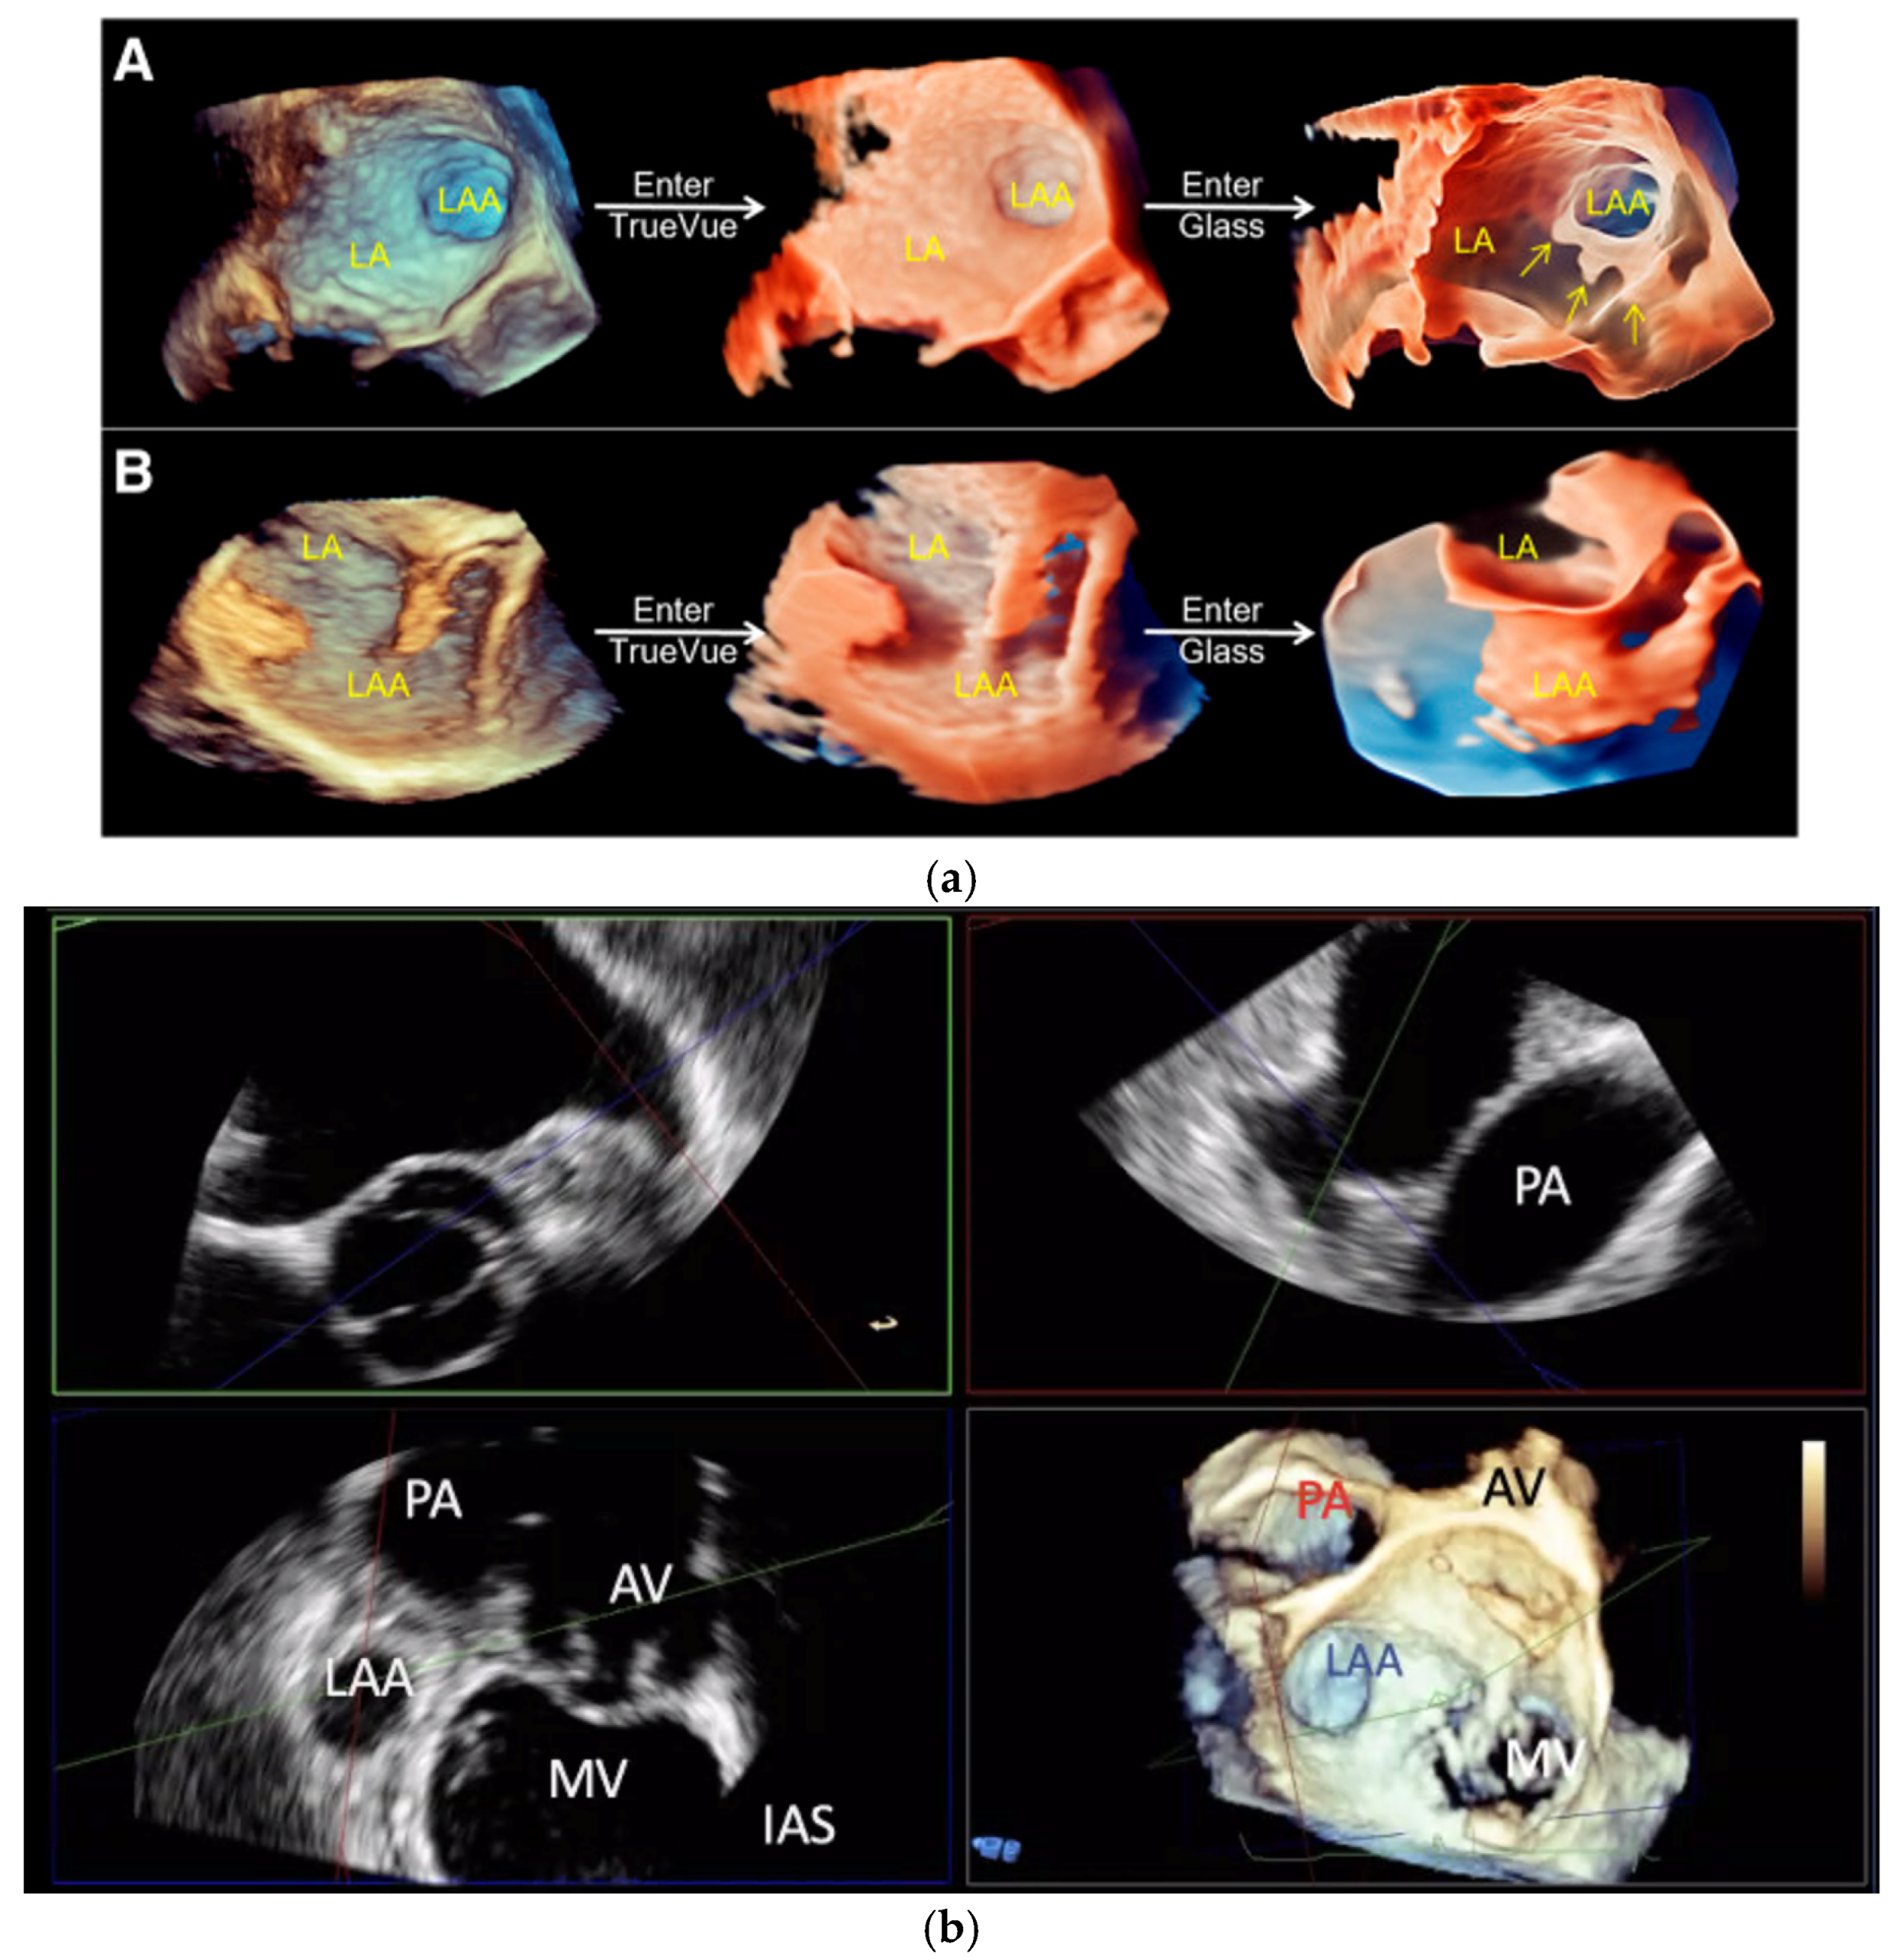

- Sun, A.; Ren, S.; Xiao, Y.; Chen, Y.; Wang, N.; Li, C.; Tan, X.; Pan, Y.; Sun, F.; Ren, W. Real-Time 3D Echocardiographic Transilluminated Imaging Combined with Artificially Intelligent Left Atrial Appendage Measurement for Atrial Fibrillation Interventional Procedures. Front. Physiol. 2022, 13, 1043551. [Google Scholar] [CrossRef]

- Okafor, J.; Rana, B.S. Importance of Echocardiography in Navigating Left Atrial Appendage Function, Thrombus Exclusion and Percutaneous Closure. Clin. Res. Cardiol. 2024, 1–3. [Google Scholar] [CrossRef]

- Nucifora, G.; Faletra, F.F.; Regoli, F.; Pasotti, E.; Pedrazzini, G.; Moccetti, T.; Auricchio, A. Evaluation of the Left Atrial Appendage with Real-Time 3-Dimensional Transesophageal Echocardiography Implications for Catheter-Based Left Atrial Appendage Closure. Circ. Cardiovasc. Imaging 2011, 4, 514–523. [Google Scholar] [CrossRef] [PubMed]

- Vainrib, A.F.; Harb, S.C.; Jaber, W.; Benenstein, R.J.; Aizer, A.; Chinitz, L.A.; Saric, M. Left Atrial Appendage Occlusion/Exclusion: Procedural Image Guidance with Transesophageal Echocardiography. J. Am. Soc. Echocardiogr. 2018, 31, 454–474. [Google Scholar] [CrossRef] [PubMed]